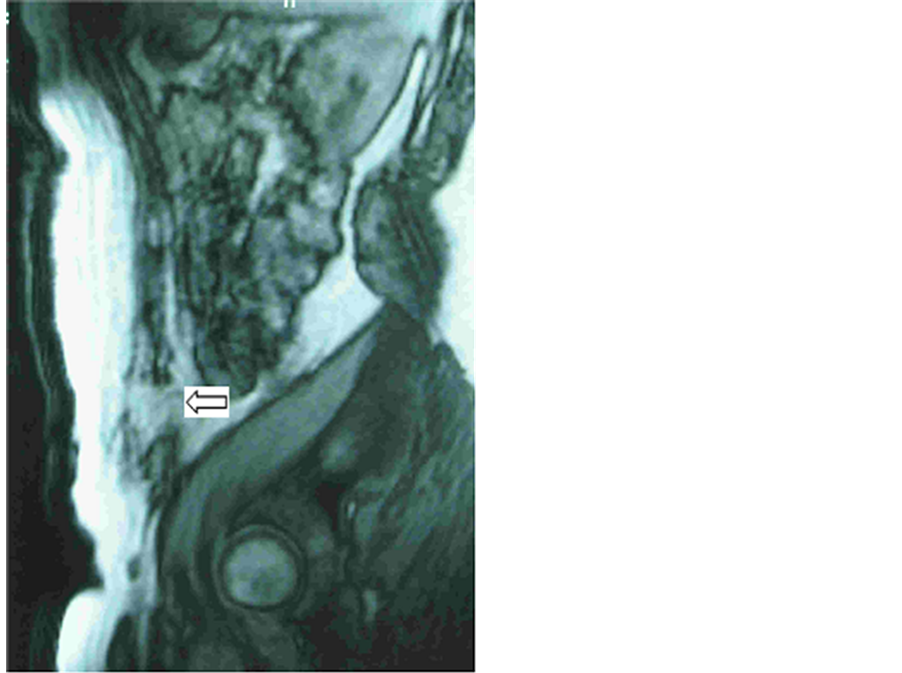

Figure 1. Preoperative MRI: sagittal view of a large incisional hernia. The arrows show the edges of the abdominal wall defect.

Preoperative MRI was very effective in showing the abdominal wall defects, not only in the axial position but in the sagittal view, allowing an appropriate evaluation of the hernia sac content, especially when the small bowel or colon were included. The evaluation of the presence and the extent of abdominal adhesions are very useful in surgery planning.

However the most important usefulness of the preoperative study was the possibility to get an accurately outline of the abdominal wall in the defect area in order to make a more effective treatment (Figure 1).